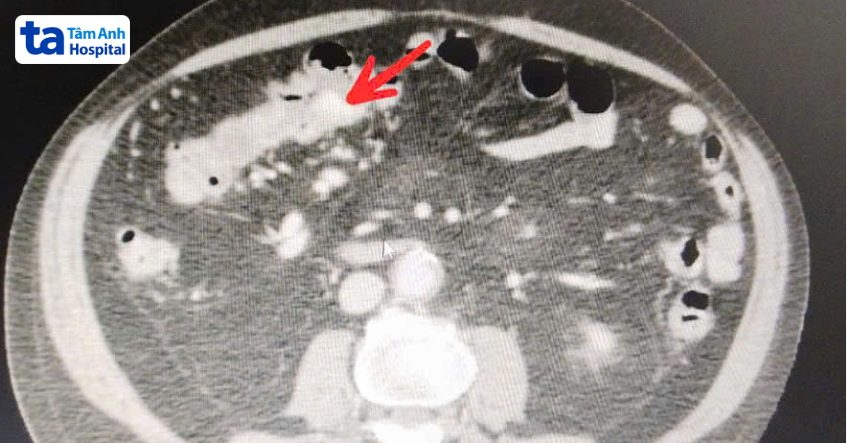

Kết quả chụp cắt lớp vi tính (CT) ổ bụng cho thấy khối dị dạng mạch máu nằm ở góc đại tràng của ông Nhất, kích thước lên đến 5 cm, vẫn đang gây chảy máu. Chỉ số hemoglobin đánh giá trình trạng thiếu máu ở mức 6,7g/dl, tức thấp hơn một nửa so với bình thường, huyết áp thấp 70/60 mmHg. Ông có nguy cơ sốc do mất máu đột ngột, thiếu máu lên não, thiếu oxy não gây co giật, khó thở, tử vong. Ông Nhất từng xuất huyết tiêu hóa nhiều lần trước đây, khả năng cao là do chưa phát hiện được khối dị dạng mạch máu ở đại tràng, theo bác sĩ Uẫn.